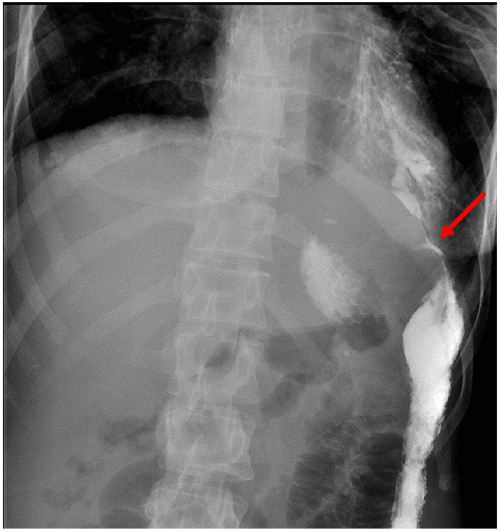

Upon admission for the aforementioned symptoms, stool studies, including C. diff, were negative. CT scan at the time of presentation was significant for pancolitis with adjacent stranding and a cavitary lung lesion in the left lower lobe measuring 2.1 × 5.4 cm with adjacent bronchiectasis and findings concerning for a colobronchial fistula (Figure 1).

Figure 1. Sagittal and Coronal High-Resolution CT Scans. Published with Permission

Image demonstrates fistulous communication between splenic flexure and left lower lobe bronchus with intact diaphragm

A classification scheme has been suggested and includes four types of colobronchial fistula. Type I involves an adhesive process with an intact diaphragm. Type II is secondary to a diaphragmatic hernia. Type III is secondary to subdiaphragmatic abscess, and type IV is secondary to colonic interposition.1 The case presented here would be classified as Type I, given the finding of an intact diaphragm on exploration. The most likely etiology is a sequela of Crohn disease previously diagnosed as ulcerative colitis. Although the pathology result was nonspecific and not entirely diagnostic of Crohn disease, we recognize that the diagnosis of IBD is clinical, with fistulation being a rare event in patients with ulcerative colitis.